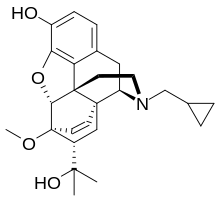

Several semi-synthetic opioids were developed in Germany in the 1910s. The first, oxymorphone, was synthesized from thebaine, an opioid alkaloid in opium poppies, in 1914.[228] Next, Martin Freund and Edmund Speyer developed oxycodone, also from thebaine, at the University of Frankfurt in 1916.[229] In 1920, hydrocodone was prepared by Carl Mannich and Helene Löwenheim, deriving it from codeine. In 1924, hydromorphone was synthesized by adding hydrogen to morphine. Etorphine was synthesized in 1960, from the oripavine in opium poppy straw. Buprenorphine was discovered in 1972.[228]